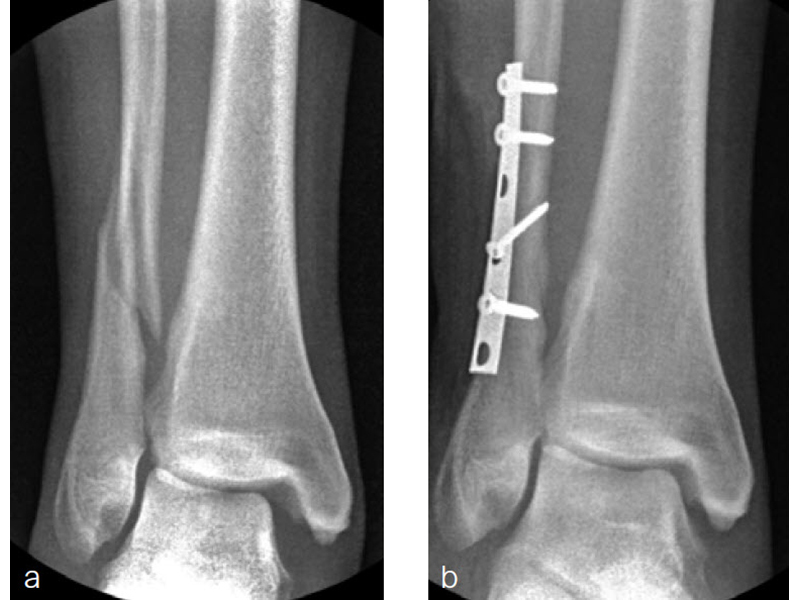

A 34-year-old woman was injured while riding a motor scooter sustaining an ankle fracture with associated syndesmotic injury (Fig 6a). The fibula was reduced anatomically and stabilized with a 1/3 tubular plate (Fig 6b). The unstable syndesmosis was reduced and provisionally stabilized with a K-wire and clamp (Fig 7) before FIBULINK Implant System implantation (Fig 8). The patient had an uneventful recovery (Fig 9).